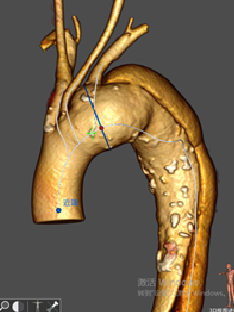

★ 病例1:主动脉弓夹层大裂口

★ 病例2:主动脉弓动脉瘤III型弓

III型弓,血管扭曲,LSA与主动脉呈锐角

术后造影无内漏,各分支形态良好,血流通畅